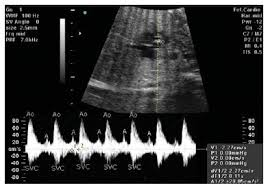

آریتمی جنینی اصطلاحی است که به وجود هرگونه اختلال در میزان ضربان قلب نوزاد اشاره دارد. این مسئله می تواند شامل افزایش ضربان قلب یا کاهش آن باشد. میزان ضربان قلب برای جنین بین 120 تا 160 در هر دقیقه است. آریتمی جنینی نادر است و ممکن است فقط در دو درصد از بارداریها دیده شود و به طور معمول موقتی بوده و قابل درمان است. به هرحال در شرایط بسیار نادر، نامنظم بودن ضربان ممکن است منجر به مرگ جنین شود.

همچنین، آریتمی جنینی، در بعضی از مراحل رشدی، طبیعی است. در طول 3 ماه دوم از بارداری، قلب نوزاد ممکن است دچار تپش های نامنظم شود. این طبیعی است و جای نگرانی وجود ندارد مگر آنکه آریتمی مدت زمان قابل توجهی ادامه پیدا کند. بعضی آریتمی ها نشان دهنده اختلالات ساختاری قلب هستند و در این مورد متخصص آزمایشات و اقدامات لازم را انجام می دهد. چنانچه میزان ضربان قلب کودک به طور مداوم بالا باشد، متخصص زنان ممکن است با تجویز دارو این مشکل را برطرف کند. دارویی که مادر در این خصوص مصرف می کند از طریق جفت به نوزاد انتقال داده می شود و میزان ضربان قلب او منظم می شود.

در صورت مشاهده آریتمی، متخصص میزان ضربان قلب و عملکردجنین را تحت نظر قرار می دهد. به هرحال ممکن است سوالات بیشتری در این زمینه وجود داشته باشد که نیازمند تحقیقات بیشتر است. در موارد نادر، متخصص زنان ممکن است مادر را برای بررسی بیشتر به متخصص قلب و عروق جنین ارجا دهد.